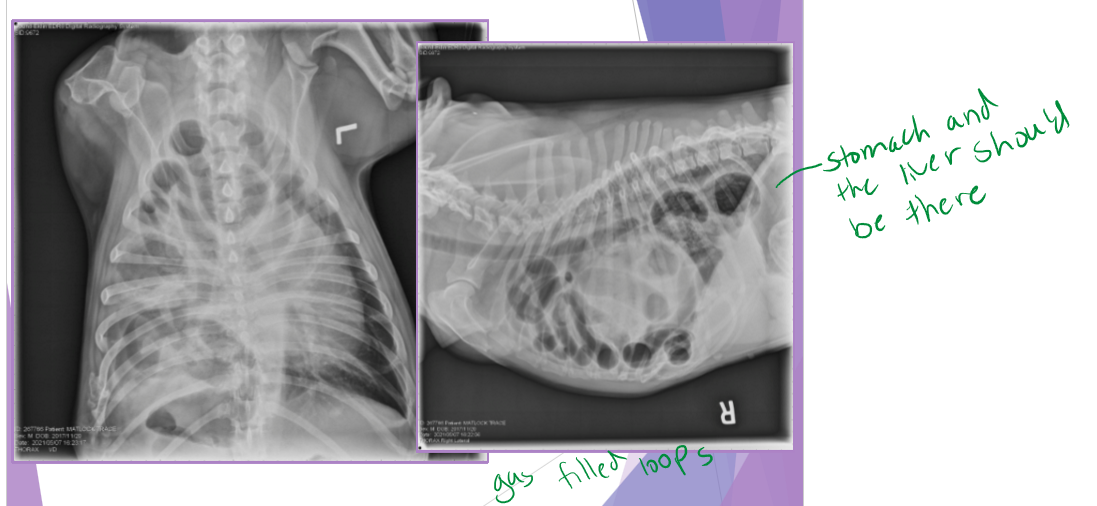

Traumatic and congenital diaphragmatic hernia

continuity of the diaphragm is disrupted

abdominal organs migrate into the thorax

thoracic radiographs (65% accurate)

pleural effusion

gas/soft tissue opacity within the thoracic cavity

stomach against the diaphragm

loss of diaphragm silhouette

Diaphragmatic hernia - Congenital

Peritoneopericardia d. hernia (PPDH)

congenital common cavity between pericardium and peritoneal cavity

diagnostic evaluation: thoracic radiographs

enlarged, globoid cardiac silhouette

± gas opacity in the cardiac silhouette